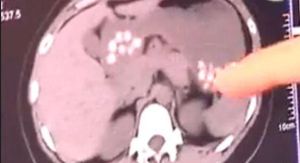

CT中難以融化的小顆粒陰影對此,青島某奶茶店工作人員透露,那些不能消化的珍珠奶茶都是化工廠生產出來的食品。說句難聽的話,就是拿皮鞋底做成的。比如皮鞋底、舊輪胎做成的。

其實,因為喝珍珠奶茶而出現的不良反應,已經有過很多先例了。2012年3月,一名浙江男孩喝珍珠奶茶引起腸梗阻,最終,不得不開刀取出。也有媒體報導過,一位江蘇女孩由於常喝珍珠奶茶,結果珍珠在胃裡粘連,形成了石塊。